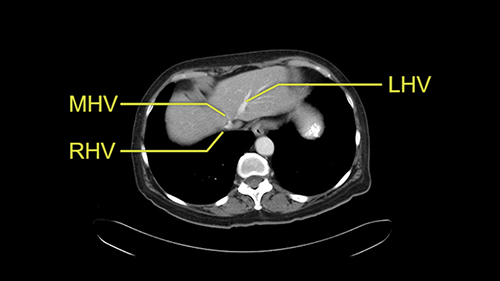

So I would then focus on the hepatic outflow because that’s the way we do the operation is by mobilizing the liver. So the vena cava looks quite normal. The right hepatic vein looks quite normal. There are no large additional outflow veins from the right lobe which would generate slowing down moments. The hepatic artery is unremarkable and is not usually an issue we can define the anatomy quite clearly at surgery.

![[RHA]](jpg/preop_sg_moment3.jpg)